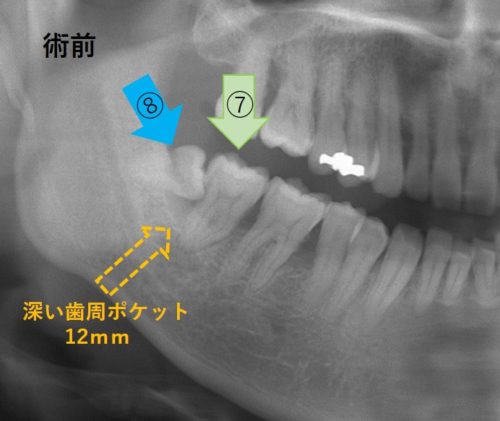

← 201.親知らずの移植!歯周病の歯を救え!